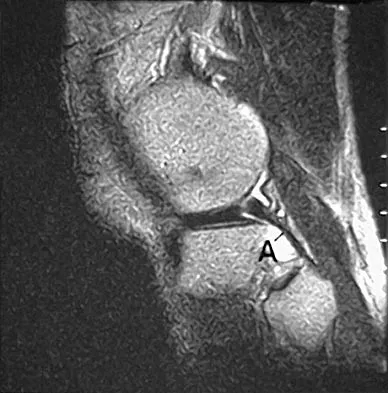

A 45-year-old man has persistent hindfoot pain that is aggravated by weight-bearing activities. History reveals that he sustained a calcaneus fracture 2 years ago, and he underwent a subtalar fusion 1 year ago. Examination reveals tenderness in the sinus tarsi and across the transverse tarsal joint. A plain radiograph and a CT scan are shown in Figures 24a and 24b. A technetium Tc 99m bone scan reveals uptake at the subtalar joint and at the transverse tarsal joints. Management should now consist of

Correct Answer: conversion to triple arthrodesis with revision of the subtalar arthrodesis.

Explanation:

The patient has a nonunion at the subtalar joint because of poor preparation of the arthrodesis site with incomplete removal of the articular cartilage. Clinically, he has arthritis at the transverse tarsal joint. Casting with a bone stimulator is not expected to result in a union of the subtalar arthrodesis. To address both the subtalar nonunion and the transverse tarsal joint arthritis, revision of the subtalar arthrodesis and conversion to a triple arthrodesis is the preferred option. Graves SC, Mann RA, Graves KO: Triple arthrodesis in older adults: Results after long-term follow-up. J Bone Joint Surg Am 1993;75:355-362. Haddad SL, Myerson MS, Pell RF IV, Schon LC: Clinical and radiographic outcome of revision surgery for failed triple arthrodesis. Foot Ankle Int 1997;18:489-499. Sangeorzan BJ, Smith D, Veith R, Hansen ST Jr: Triple arthrodesis using internal fixation in treatment of adult foot disorders. Clin Orthop 1993;294:299-307. Sangeorzan BJ: Salvage procedures for calcaneus fractures. Instr Course Lect 1997;46:339-346.